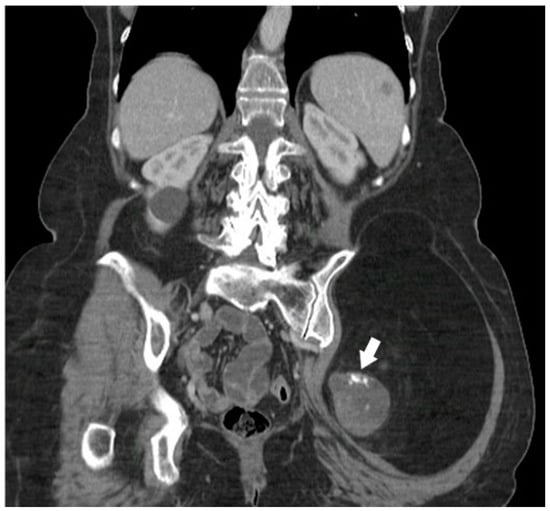

5.2.2. Primary Tumoral Calcinosis

- Fathi, I.; Sakr, M. Review of tumoral calcinosis: A rare clinico-pathological entity. World J. Clin. Cases WJCC 2014, 2, 409. [Google Scholar]

- Zanatta, E.; Desportes, M.; Do, H.H.; Avouac, J.; Doria, A.; Feydy, A.; Allanore, Y. Pseudotumoral calcinosis in systemic sclerosis: Data from systematic literature review and case series from two referral centres. Semin. Arthritis Rheum. 2020, 50, 1339–1347. [Google Scholar]

- Daumas, A.; Rossi, P.; Ariey-Bonnet, D.; Bernard, F.; Dussol, B.; Berbis, P.; Granel, B. Generalized calcinosis in systemic sclerosis. QJM Int. J. Med. 2014, 107, 219–221. [Google Scholar]